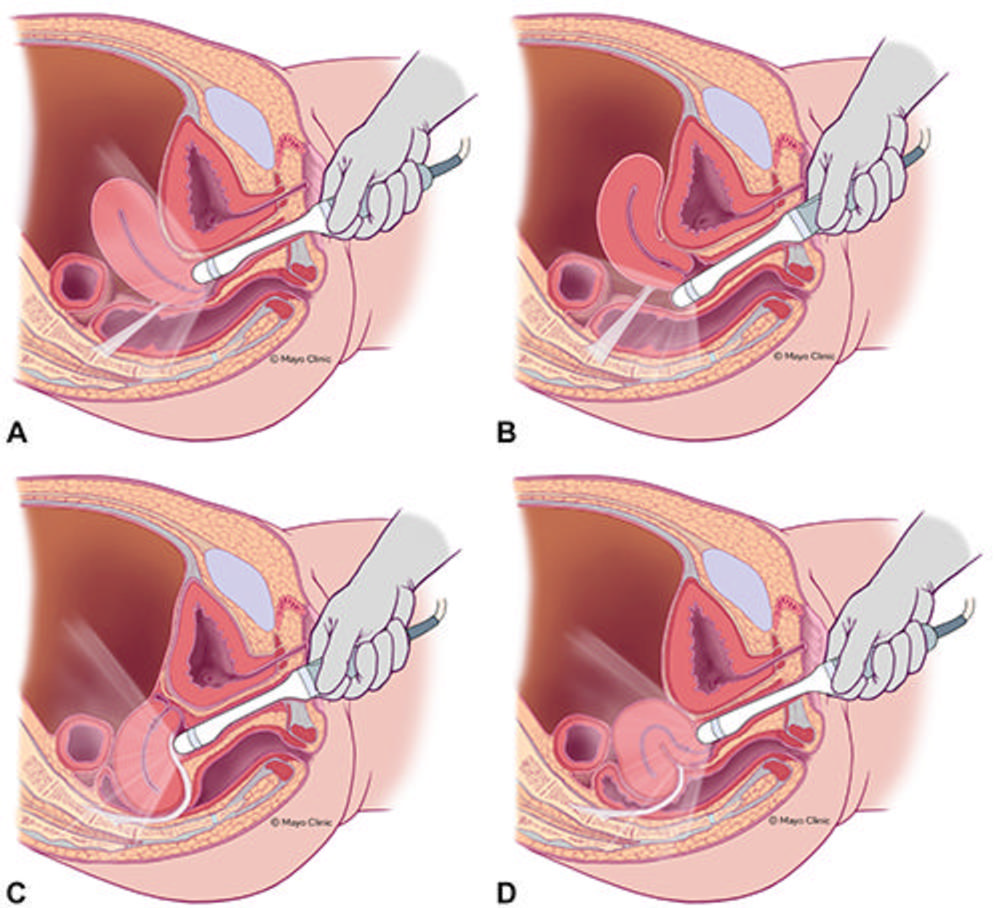

Figure 2. Illustration shows how to position the transvaginal sonography transducer based on uterine position and uterosacral ligament (USL) anatomy variations (light gray band). The relative relationship between the transducer, USLs, and cervicouterine junction is demonstrated for (A) anteverted uterus, anterior fornix transducer position; (B) anteverted uterus, posterior fornix transducer position; (C) retroverted uterus, posterior fornix transducer position; and (D) anteflexed/retroverted uterus, anterior fornix transducer position. Reprinted, with permission, from Young SW, Groszmann Y, Dahiya N, et al. “Sonographer-acquired ultrasound protocol for deep endometriosis” Abdominal Radiology.

Figure 6. Illustration shows the uterine sliding maneuver, posterior fornix transducer position, anteverted uterus (A) and retroflexed uterus (B) . Adapted, with permission, from Young SW, Groszmann Y, Dahiya N, et al. “Sonographer-acquired ultrasound protocol for deep endometriosis” Abdominal Radiology.